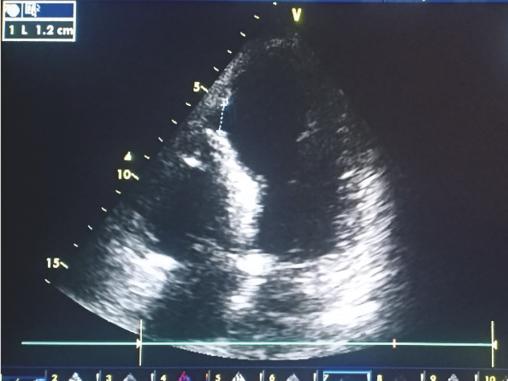

Cet homme de 70 ans à très haut risque cardiovasculaire cumulant diabète, hypertension artérielle et tabagisme, consultait 48 heures après une douleur thoracique angineuse, pour une dyspnée de repos. À l’examen on notait des signes de décompensation cardiaque droite, avec à l’auscultation un souffle holosystolique râpeux en parasternal gauche, irradiant en rayon de roue. L’électrocardiogramme montrait des séquelles d’ischémie en antérieur étendu et l’échocardiographie visualisait une large communication interventriculaire (CIV) musculaire avec shunt gauche-droite (fig. 1 et 2 ). La coronarographie montrait des lésions bitronculaires. La revascularisation chirurgicale et la fermeture de la CIV étaient réalisées sous circulation extracorporelle avec des suites opératoires simples.

La communication interventriculaire compliquant un infarctus du myocarde est une complication rare mais redoutable, associée à un taux de mortalité très élevé qui avoisine 97 % à 30 jours de l’infarctus.1 Son diagnostic repose sur la suspicion clinique et la confirmation échocardiographique.